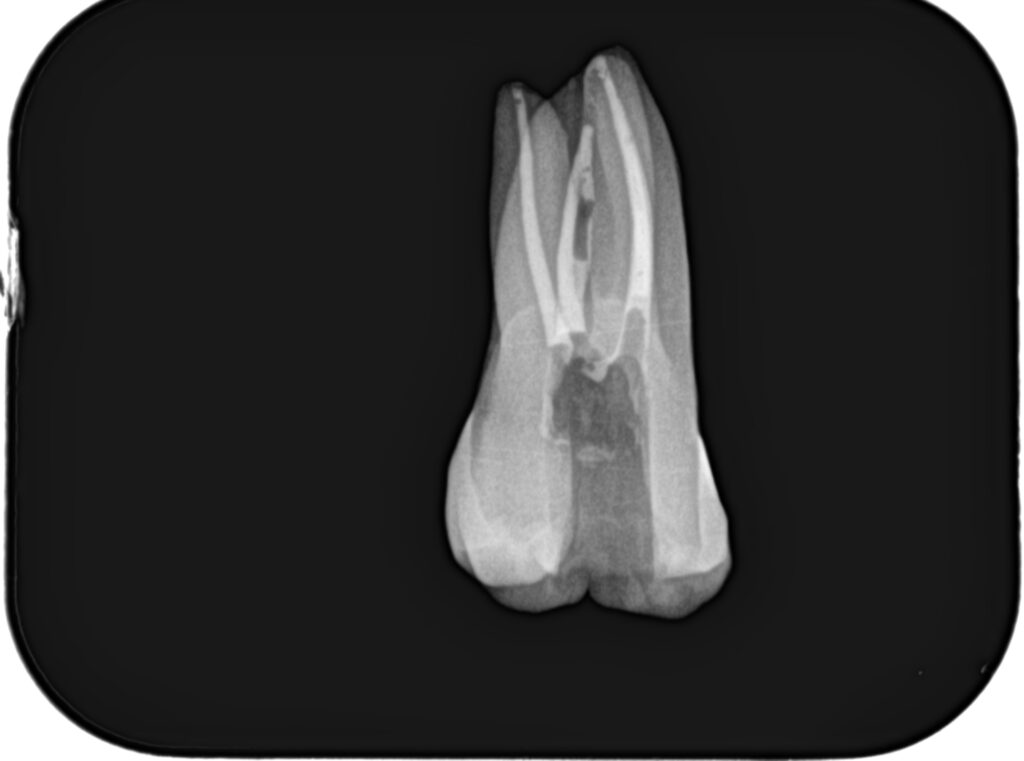

まず作業長の測定方法を行うまでを解説した。

その後、根管形成である。

上記動画では、細い穿通させた根管を号数を下げずにWave One Gold #25だけで作業長まで形成している。

根管形成が終了すれば、根管充填だ。

日曜日は実習を行った。

土曜日の内容を投影した実習であった。

2本の歯牙で実習し、あっという間に1日は終了した。